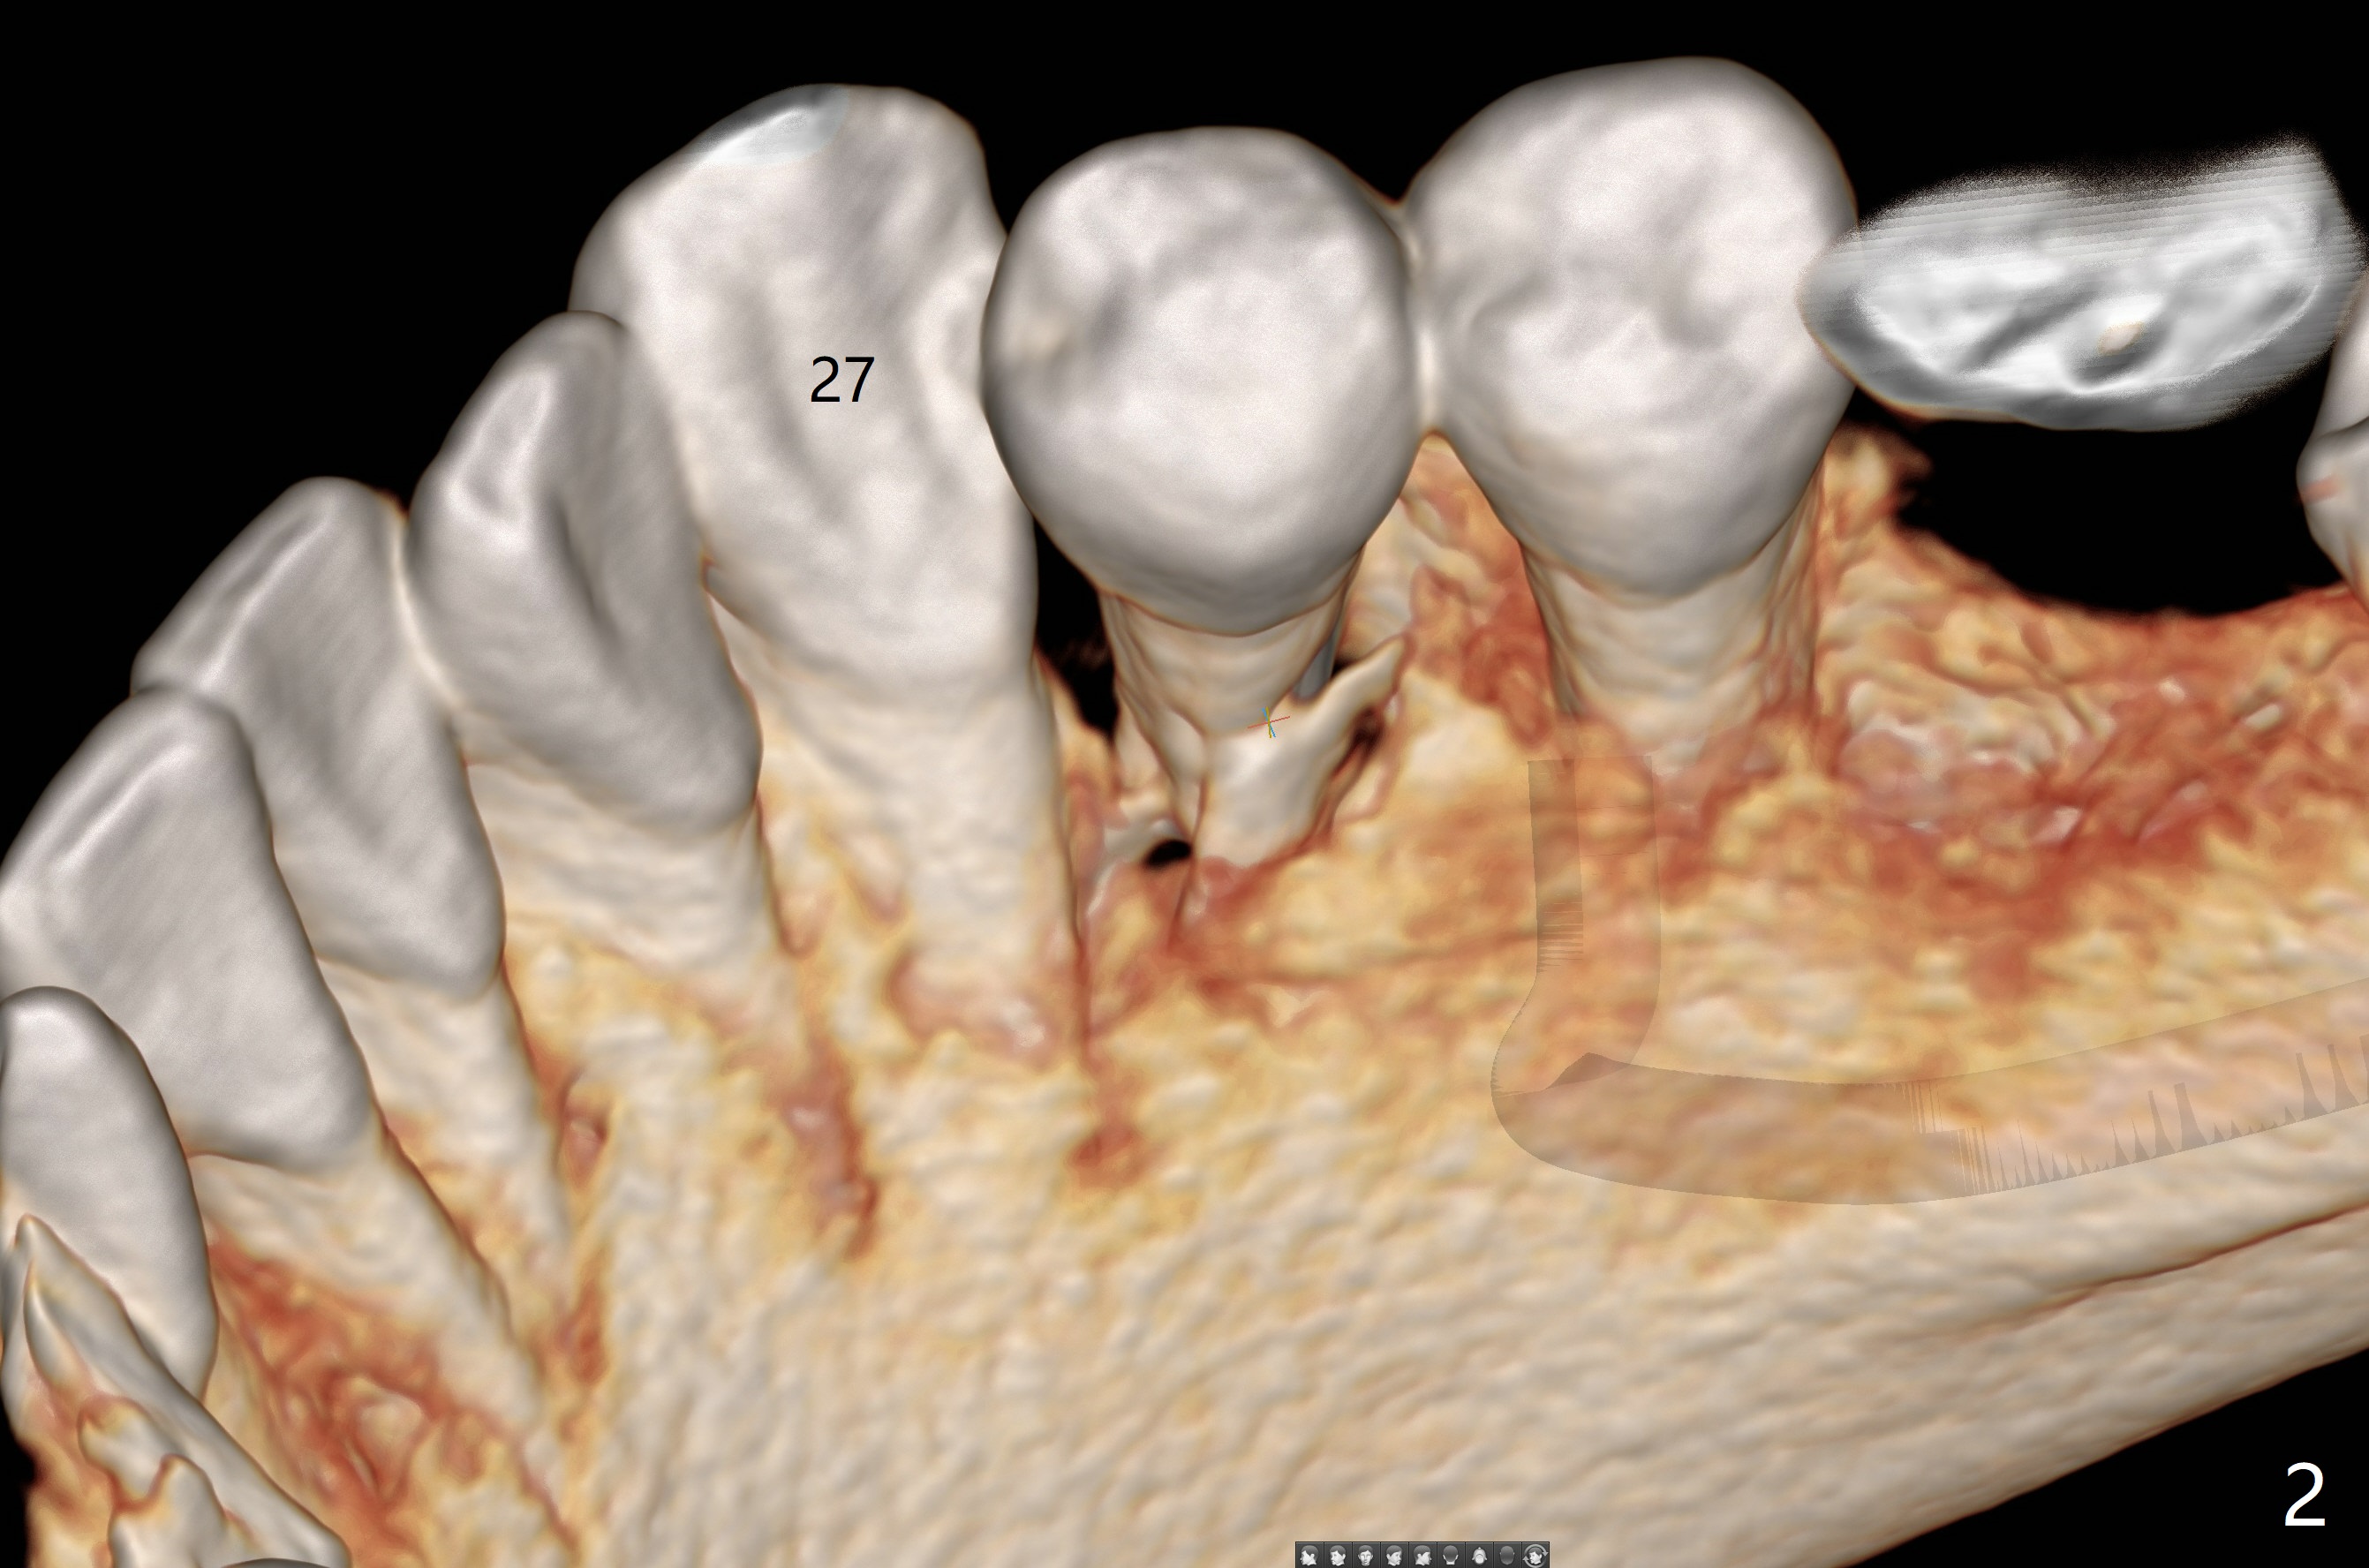

A -year-old man seeks treatment for the tooth #28 with severe bone loss (Fig.1 islands of bone remaining in the mesial surface of the tooth #27, reossification center for grafted bone). The tooth #28 has oblique root fracture (Fig.2 lingual view). One of treatment options is to place an immediate implant (green) at #28 as lingual as possible (Fig.3,4 (coronal section, after extraction (black area))). Sticky bone is placed buccal (Fig.5 red); some of bone graft will be pressed into the space between implant threads (arrowheads, bone and implant contact area expectedly to be higher than delayed placement due to less pressure to the native bone). In spite of severe bone loss between #27 and 28 (Fig.6 (sagittal section) after extraction), the crestal bone appears to exist in the mesial surface of #27 (*). With placement of an abutment (Fig.7 pink) and an immediate provisional (white), bone graft is packed as high as supracrestal (red). Restoration of the crest is expected to be better than socket preservation.